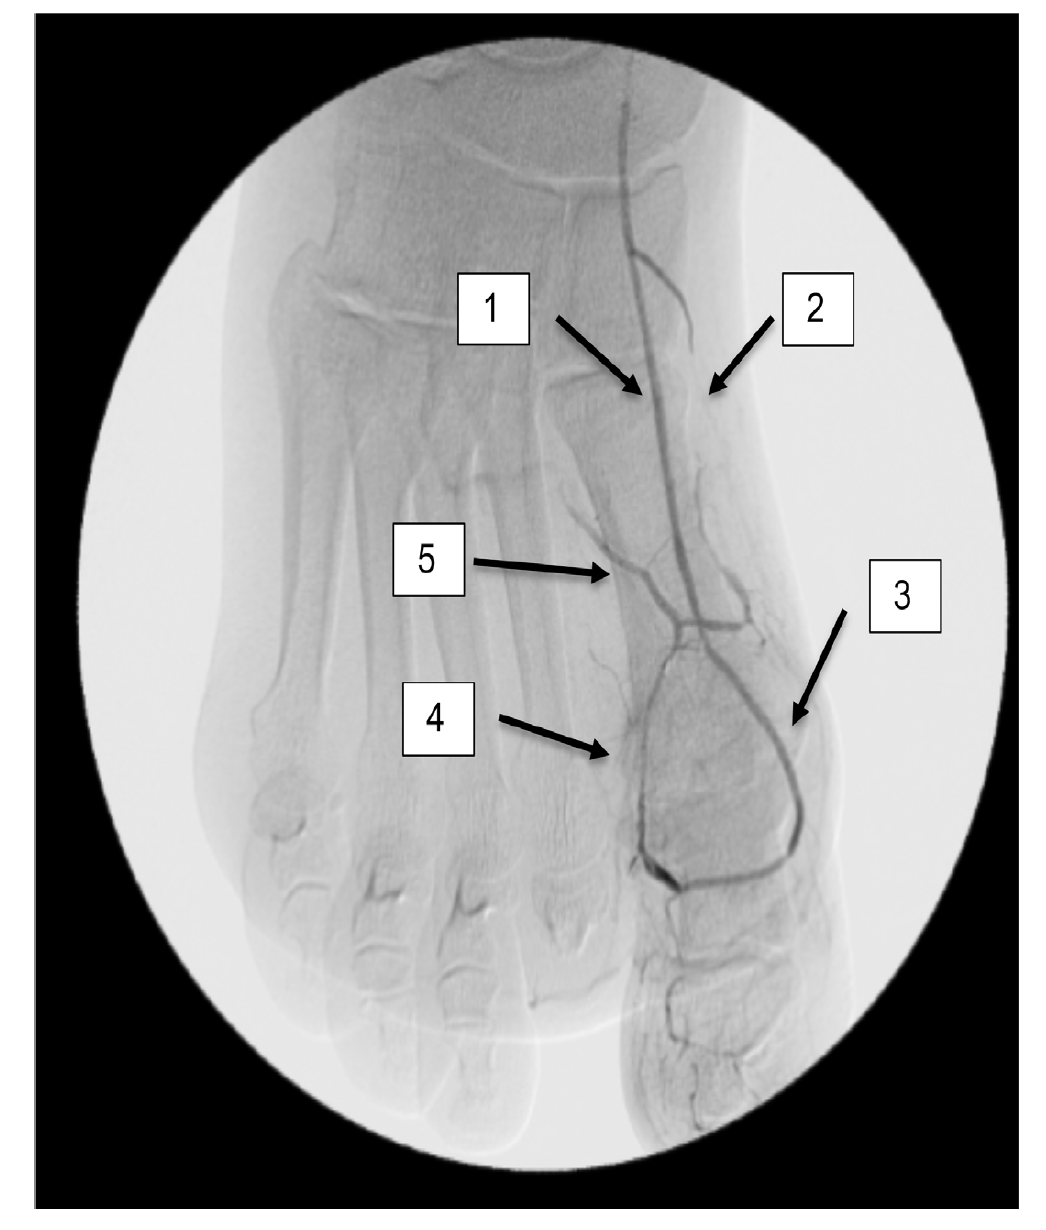

A right lower-extremity angiogram was performed using ultrasound guidance for antegrade access of the proximal superficial femoral artery (Figure 2A). Fluoroscopic acquisition demonstrated no significant disease in the superficial femoral artery (Figure 2B) and popliteal artery (Figure 2C), with no significant stenosis seen in the anterior tibial artery, PTA, and peroneal artery (Figure 2D). Pedal angiography demonstrated a complete pedal-plantar loop formed by the DPA and the lateral plantar artery (LPA) (Figure 2F).

However, the entirety of the medial plantar artery (MPA) distribution was chronically occluded shortly after take-off (Figure 2E and Figure 2F). Super-selective angiography revealed chronic total occlusion of the medial branch of the first common plantar digital artery arising from the first plantar metatarsal artery (Figure 2G). Angiography also revealed an occluded accessory branch arising medially from the superficial branch of the MPA.

The anatomy of the arteries supplying the hallux is complex, with variants being common. In this patient, an atypical accessory branch arising from the superficial branch of the MPA was present. While the arterial anatomy of hallux-supplying arteries and its corresponding variants are not readily discussed in recent literature, certain textbooks do depict an accessory branch arising from the superficial branch of the MPA.2 The accessory branch of this patient, in particular, communicated with the first dorsal metatarsal artery arising from the DPA (Figure 2F) and the superficial branch of the MPA communicated with the medial branch of the first common plantar digital artery arising from the LPA (Figure 4C). In general, using the angiosome concept, the blood supply to the hallux consists of 3 main avenues: (1) the first dorsal metatarsal branch arising from the DPA; (2) the plantar digital arteries arising from the first plantar metatarsal artery, which is a branch of the LPA; and (3) the superficial branch of the MPA.3,4 The latter 2 sources of blood supply were absent in this case.